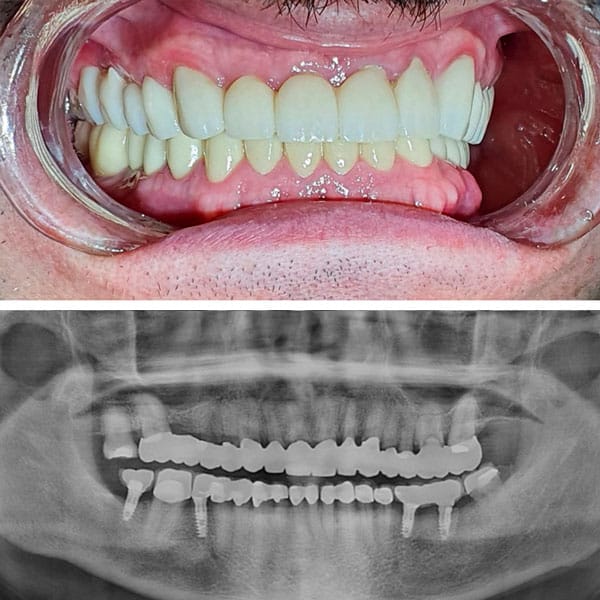

CASOS CLÍNICOS